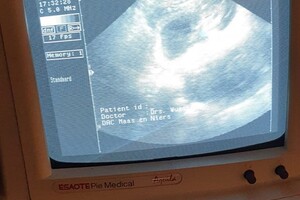

de dierenarts mocht Dakota eerst scheren, dit had ze nog niet eerder meegemaakt, maar ze vondt het niet zo erg, daarna heeft de dierenarts de scan gemaakt:

Ze is drachtig. het blijft moeilijk te zien hoeveel puppy's we kunnen verwachten, maar de dierenarts gaf aan dat we een mooi nest krijgen: niet te groot en niet te klein nest, ze ging uit van 4 a 5 puppy's. Dierenarts verwacht dan ook geen complicaties en een natuurlijke bevalling.